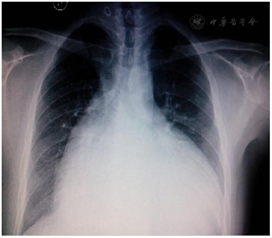

入院后完善检验提示三大常规、凝血六项、肾功能、血气分析、心肌损伤标志物及BNP正常。而肝功能检验提示:ALP、GGT、TBil等显著增高,提示肝功能异常。胸部X片提示:心界明显扩大,心胸比约为0.81(图1)。心电图提示:心房颤动;电轴右偏;完全性右束支阻滞;心脏顺钟向转位;T波改变窦性心律,T波低平(图2)。进一步完善心脏彩超:左心房32 mm、左心室40 mm;右心房横径100 mm、上下径106 mm;右心室前后径65 mm、横径81 mm、上下径62 mm;肺动脉主干24 mm,右室流出道60 mm;右心室EF 34%;左心室EF 66%,室壁未见节段性运动异常;三尖瓣:瓣环52 mm,关闭时瓣口对合差,反流面积37 cm2,流速190 cm/s,压差15 mmHg(图3)。腹部彩超:肝脏:右叶斜径16 mm,肝段面增大,肝静脉明显增宽(右支2.4 mm,中支2.2 mm,左支2.0 mm);下腔静脉内径4.0 mm;胆囊壁粗糙增厚;胰、脾及双肾未见异常。

手术前后彩超对比提示右心显著缩小,提示治疗后患者右心结构得到恢复。手术前后胸部X片对比提示心影缩小,心胸比从0.81下降到0.72。结合患者心功能、后期复查结果,提示冠脉重建后右心心肌血供恢复,心肌重塑,大小恢复。术后3个月复查心电图:阵发性房性心动过速(房室传导比例呈2:1传导);电轴右偏;完全性右束支传导阻滞;ST-T改变。通过治疗患者右心大小逐渐恢复正常,心功能恢复,日常生活无明显受限,规律服药、定期复查中,对治疗效果满意。